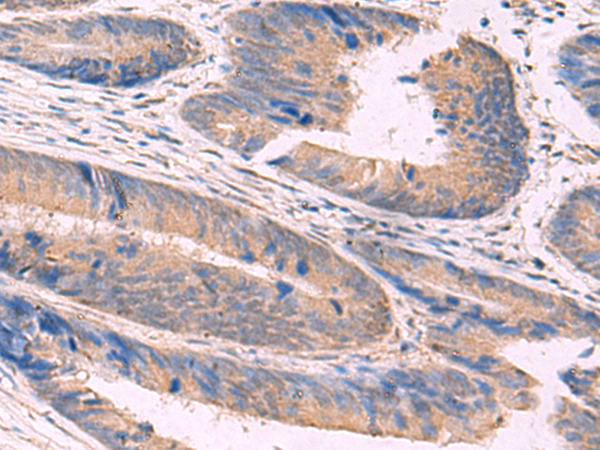

IHC (Immunohistochemistry)

(The image is immunohistochemistry of paraffin-embedded Human liver cancer tissue using 47689(NIPSNAP1 Antibody) at dilution 1/50.(Original magnification: 200))